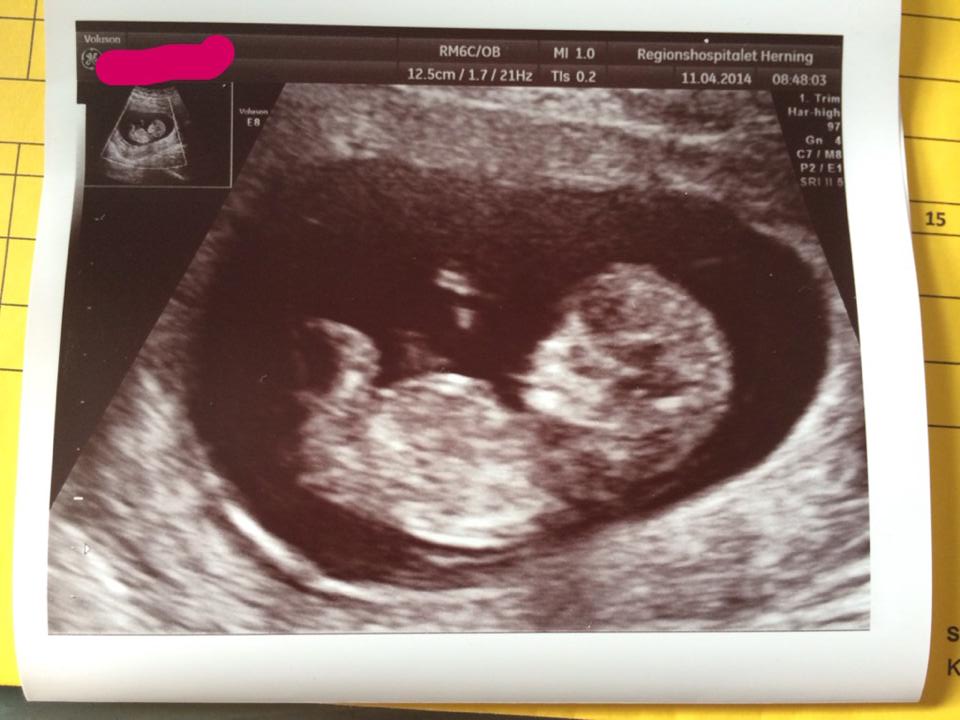

What Does Nt Mean On Baby Scan / 3D/4D Baby Scan Clinic located at 130 Harley Street ... : This is sometimes called a nuchal translucency scan.. The amount of fluid is measured during an nt ultrasound scan: The amount of fluid is measured during a nuchal translucency (nt) ultrasound scan: I had my 12 week scan today and baby is measuring 13+3weeks. The nt scan is an ultrasound done in the first trimester to determine your baby's risk of having down syndrome and some other chromosomal abnormalities. Among the many terms you will learn and become familiar with is a nuchal scan.

It helps doctors determine if a baby is statistically more likely to have a chromosomal abnormality. An increased amount of fluid may show that your baby has a physical problem or chromosome problem. My doc doesn't recommend the nt scan until after 12 weeks for that reason. It is a special ultrasound scan which is performed to specifically measure a tiny bit of fluid that lies under the baby's skin behind the neck known as the nuchal translucency (nt). The dating scan can include a nuchal translucency (nt) scan, which is part of the combined screening test for down's syndrome, if you choose to have this screening.

Baby, Borneo or Bust. . .: Genetic Counseling, the NT Scan ... from 4.bp.blogspot.com Between 11 weeks and 13 weeks plus six days of pregnancy An increased amount of fluid may show that your baby has a physical problem or chromosome problem. The anatomy scan is a level 2 ultrasound, which is typically performed on pregnant women between 18 and 22 weeks. The starting point for the calculation of risk is your age at the time your baby is due. A special ultrasound, called a nuchal translucency screening, measures the back of the baby's neck. The only stuff that relates to the baby itself are fhr (foetal heart rate or the babys heart beat) and crp (crown to rump length used in dating the baby). A nuchal translucency scan is part of the ultrasound scan that most pregnant women have at around 12 weeks of pregnancy. It helps doctors determine if a baby is statistically more likely to have a chromosomal abnormality.

This is the ultrasound typically completed at the 12 week mark of pregnancy.

The screening test for down's syndrome used at this stage of pregnancy is called the combined test. If the next set of test gives a negative result then chances of actually having an affected baby are very low as the false negative rates of tests is not usually very high. Since chromosomal abnormalities can result in impaired cardiovascular development, a nuchal translucency scan is used as a screening, rather than. If you have missed on the viability scan, not to worry nt scan also called as the first trimester scan will give you a detailed health status about your baby and your pregnancy too. A maternal blood sample will also be taken and you may also be offered an evaluation of the baby's nasal bone. This is called a false positive. The ultrasound scan records your baby's nuchal translucency measurements, and can also examine your baby in some detail to check whether many of the main organs are developing normally. Among the many terms you will learn and become familiar with is a nuchal scan. The scan takes place between 10 and 14 weeks of pregnancy; It is a special ultrasound scan which is performed to specifically measure a tiny bit of fluid that lies under the baby's skin behind the neck known as the nuchal translucency (nt). They referred me to genetic counselor which i have an appt with on friday. The amount of fluid is measured during a nuchal translucency (nt) ultrasound scan: This test measures the size of the clear tissue, called the nuchal translucency, at the back of your.

A nuchal translucency screening, or nt screening, is a specialized routine ultrasound performed at the end of the first trimester of pregnancy. The dating scan can include a nuchal translucency (nt) scan, which is part of the combined screening test for down's syndrome, if you choose to have this screening. It is a special ultrasound scan which is performed to specifically measure a tiny bit of fluid that lies under the baby's skin behind the neck known as the nuchal translucency (nt). A nuchal scan or nuchal translucency (nt) scan/procedure is a sonographic prenatal screening scan to detect chromosomal abnormalities in a fetus, though altered extracellular matrix composition and limited lymphatic drainage can also be detected. It involves a blood test and measuring the fluid at the back of the baby's neck (nuchal translucency) with an ultrasound scan.

This is the ultrasound typically completed at the 12 week mark of pregnancy. The amount of fluid is measured during an nt ultrasound scan: I had my 12 week scan today and baby is measuring 13+3weeks. My doc doesn't recommend the nt scan until after 12 weeks for that reason. Since chromosomal abnormalities can result in impaired cardiovascular development, a nuchal translucency scan is used as a screening, rather than. The nuchal translucency scan (nt scan) is an ultrasound that may detect the risk of some chromosomal abnormalities in the foetus. A special ultrasound, called a nuchal translucency screening, measures the back of the baby's neck. The anatomy scan is a level 2 ultrasound, which is typically performed on pregnant women between 18 and 22 weeks. One of the ways to detect congenital disorders or defects in unborn baby is nuchal translucency (nt) scan. Due to my schedule i was trying to get in at 10w and he really wanted me to wait until 12w because he said the nt space wasn't accurate before then (from his experience) due to the baby being too small. This is sometimes called a nuchal translucency scan. The first scan is sometimes called the dating scan. It should not be confused with the nuchal fold, which is seen in the second trimester.

A nuchal translucency ultrasound (commonly called a nuchal scan or nt scan) is an ultrasound performed between 11.5 and 13 weeks 6 days gestation. If you have missed on the viability scan, not to worry nt scan also called as the first trimester scan will give you a detailed health status about your baby and your pregnancy too. This is sometimes called a nuchal translucency scan. Between 11 weeks and 14 weeks of pregnancy or when your baby measures between 45mm (1.8in) and 84mm (3.3in) A nuchal scan or nuchal translucency (nt) scan/procedure is a sonographic prenatal screening scan to detect chromosomal abnormalities in a fetus, though altered extracellular matrix composition and limited lymphatic drainage can also be detected.

This is sometimes called a nuchal translucency scan. Between 11 weeks and 13 weeks plus six days of pregnancy If the screen indicates that your baby may have a problem, you can decide whether or not to have cvs or amnio for a diagnosis. The nuchal translucency scan is certainly not determinative of whether the baby has a chromosomal defect. It helps doctors determine if a baby is statistically more likely to have a chromosomal abnormality. The screening test for down's syndrome used at this stage of pregnancy is called the combined test. The anatomy scan is a level 2 ultrasound, which is typically performed on pregnant women between 18 and 22 weeks. Nuchal translucency is a screening test to determine risk of chromosome abnormalities in a fetus. A look at what your scans will involve. The scan takes place between 10 and 14 weeks of pregnancy; The report that the midwife gets with the scan gives you all the information you need did you read it with the midwife? The nuchal translucency measurement was 3.6mm. When the nt is greater than 3.5 mm, there is a 1 in 5 chance of a chromosome abnormality such as turner or down syndrome, or trisomy 18.